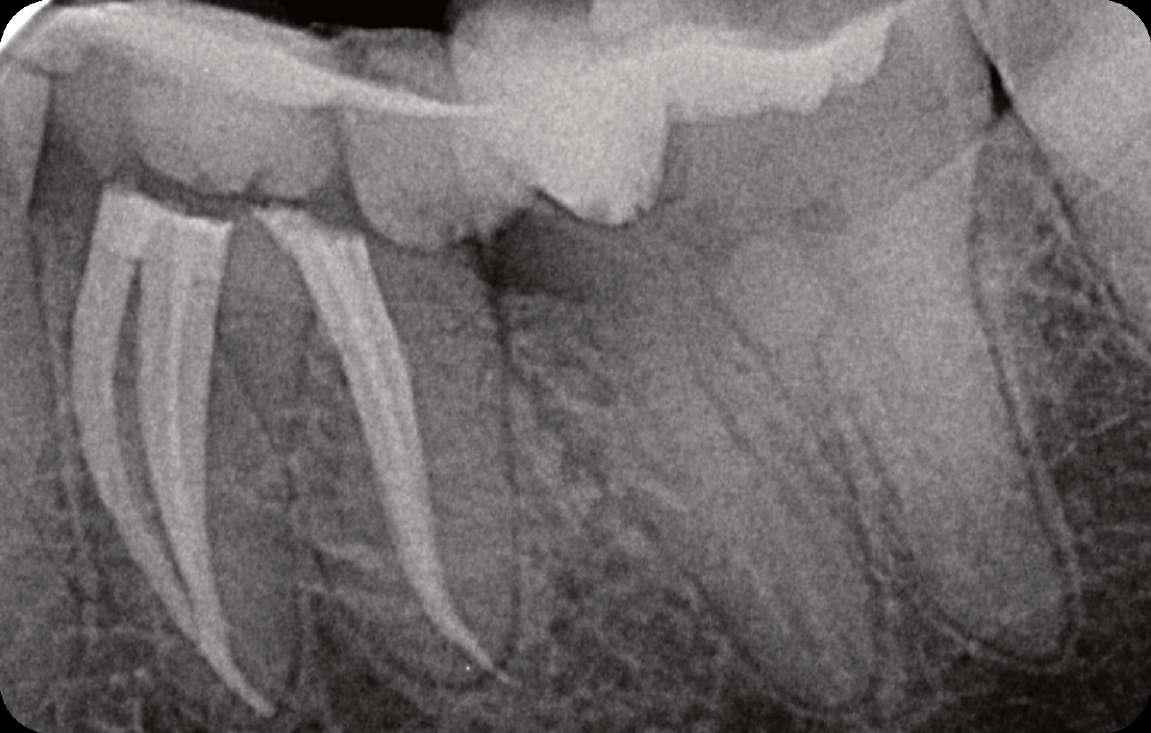

Röntgenologischer Befund: Therapie

Das präoperativ angefertigte diagnostische Röntgenbild zeigt eine insuffiziente Amalgamfüllung im distalen Approximalraum. Die mesiale Wurzel weist eine periapikale Osteolyse auf (Abbildung 1).

Abbildung 1: Präoperative Diagnostische Aufnahme

Röntgenologischer Befund: Zahn 27 weist eine apikale Aufhellung im Sinne einer chronischen apikalen Parodontitis auf (Abbildung 6).

Abbildung 6: Präoperative diagnostische Aufnahme